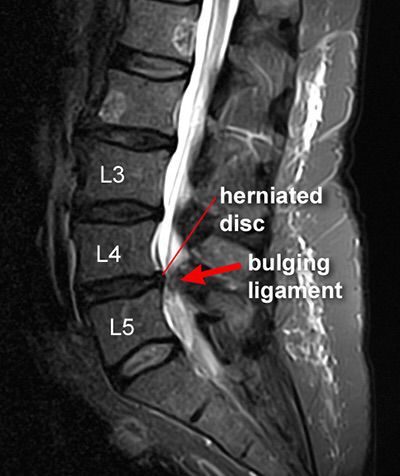

It is common in middle aged and older men. Causes include degenerative changes, trauma, neck/back strain. Most common (95%) is in lumber region especially at L5-S1. History: * Patient presents with severe, electricity-like lower back pain, usually preceded by several months of aching, 'discogenic' pain. * ⬆️Pain = by inc. intra-abdominal pressure = by passive straight leg raise = by crossed straight leg raise * Associated with sciatica, paresthesias, muscle weakness or spasm. * Large midline herniations can cause cauda equina syndrome which is a surgical emergency. Diagnosis: * By positive passive straight leg raise. * MRI is the preferred test. * Obtain ESR and plain x ray if other causes of lower back pain are suspected. Treatment: * Best initial treatment is NSAID in scheduled doses, physical therapy and local heat. * Epidural steroid injection or nerve block is useful in cases not responding to initial therapy. * Surgery is most definitive treatment.